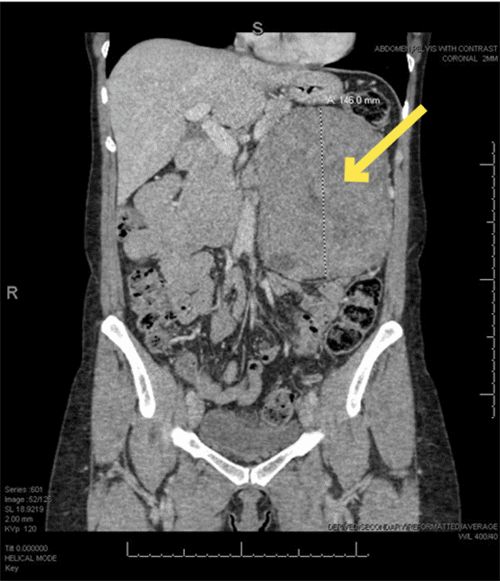

The patient was referred to the surgical oncology service for preoperative evaluation and operative planning for the excision of the mass. Given the size and symptomatic nature of the mass, a decision was made to pursue a more radical surgical excision instead of a percutaneous biopsy. Preoperative computed tomography of the abdomen and pelvis was obtained to assess the anatomic planes for resection because the MRI images performed at the previous medical facility were not readily available (Figure 2).

Figure 2. CT with IV Contrast Images of Mass. Published with Permission

A) Axial at its largest dimensions; images were used for preoperative planning and visualization of planes of dissection

B) Coronal at its largest dimensions; images were used for preoperative planning and visualization of planes of dissection